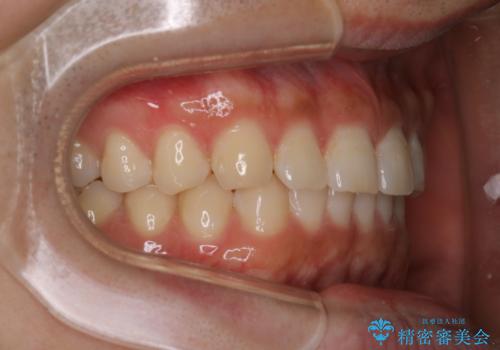

【インビザライン】正中離開を治したい

再矯正ということでがたつきはなくきれいに並んでいましたが、上下のアーチ(歯列弓)の大きさのバランスが悪く、結果的に後戻りの原因になってしまっていました。今回は下のアーチを小さくするためにIPRを行い、かみ合わせのバランスを治しながら前歯の隙間を閉じました。